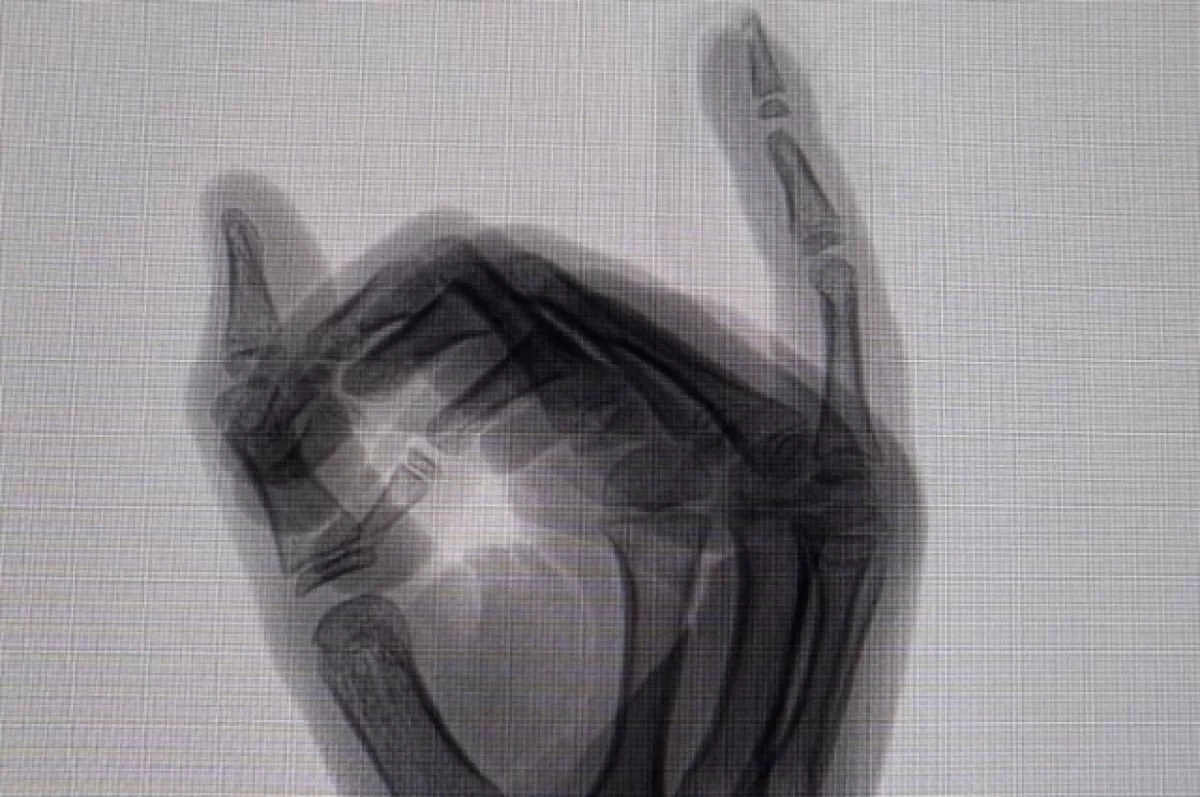

«Когда нам сняли швы, мы поняли, что палец зашили, мягко говоря, не так, как нужно. На снимке все прояснилось, а наши мечты сохранить ногтевую пластику рухнули. А теперь нам предстоит экстренная операция. В Бийске нам не могут помочь, едем в федеральную травматологию. Шанс восстановить пальчик очень мал. Скорее всего, будет ампутация торчащей кости. Это значит, что ребенок еще больше лишится части пальца», — рассказала мама.